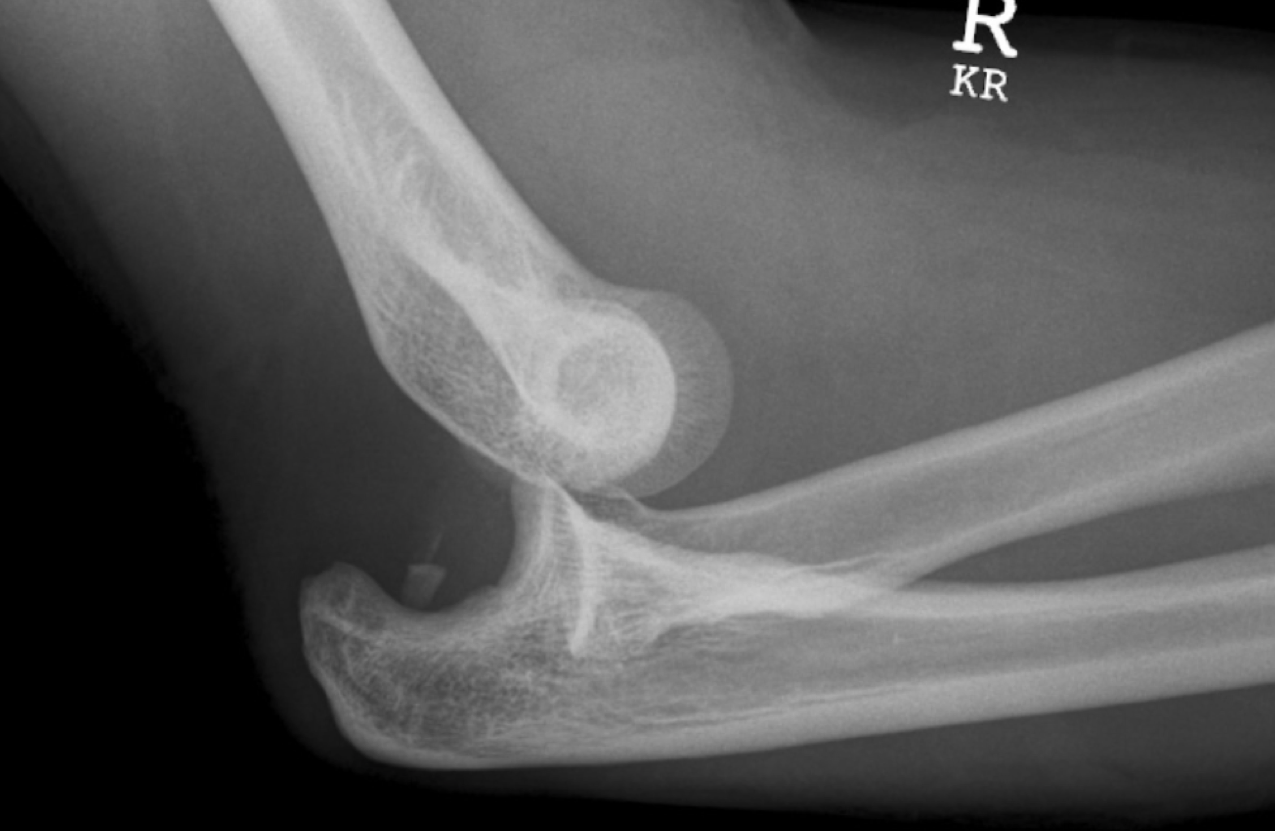

What does this radiograph show?

Elbow dislocation